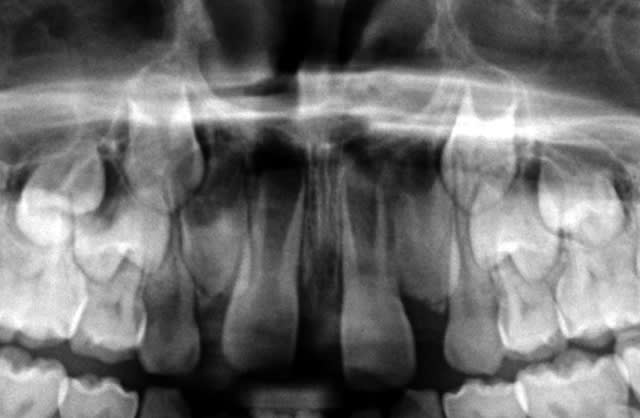

Ici, enfant de 8 ans adressé par ortho qui veut baguer pour créer de l'espace pour 12-22.

la panoramique montre des racines très peu évoluées et la fermeture du diastème semble prématurée, à mon humble avis.

Salut, pour les enseignants du CETO le frein est un moteur de croissance qu'il ne faut pas retirer, et les diastèmes médians entre les centrales sont un signe majeur d'encombrement. Quand on voit ta pano on peut se dire qu'ils ont peut être bien raison.